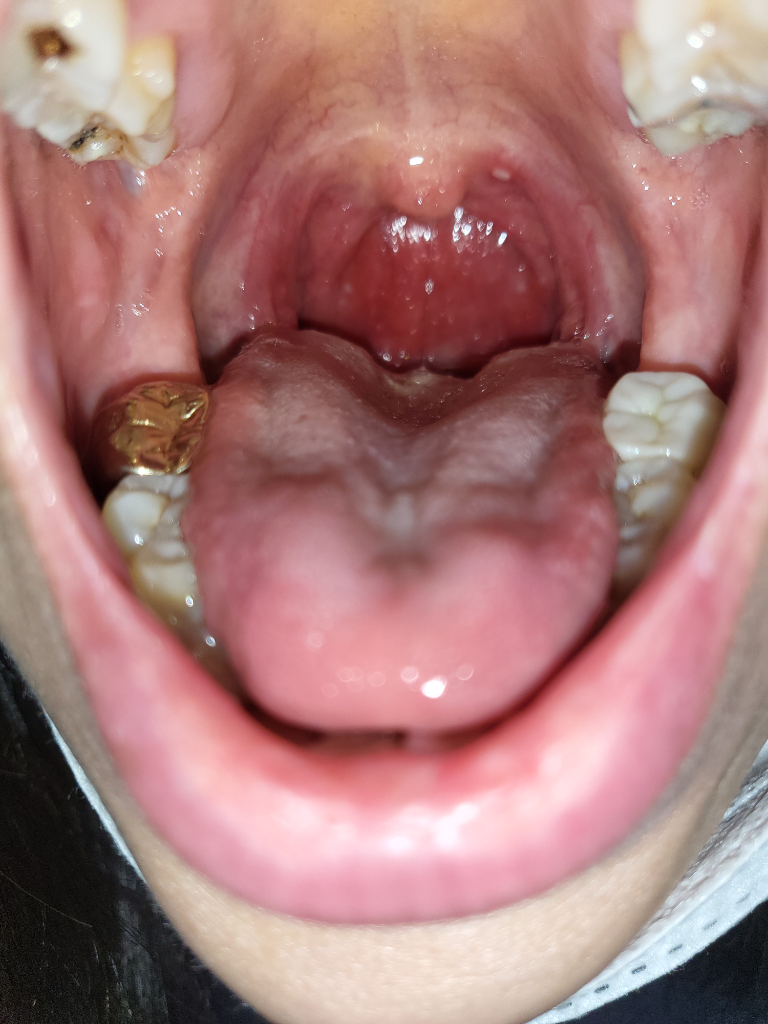

요번에 편도염이 아주심하게와서 아직도 치료중인데요..편도염 이후 목젖옆에 조그마한 혹이 생겼어요..이비인후과에선 아직 물어보진 못했고 선생님도 별 말씀이 없으시네요.. 진료를 따로 받아봐야 맞는거겠죠?..

구내염이 생긴 것 같아요. 아프지 않다면 그냥 놔두셔도 괜찮습니다. 저절로 없어질 거에요. 다음에 병원 가시면 한번 물어만 보세요.